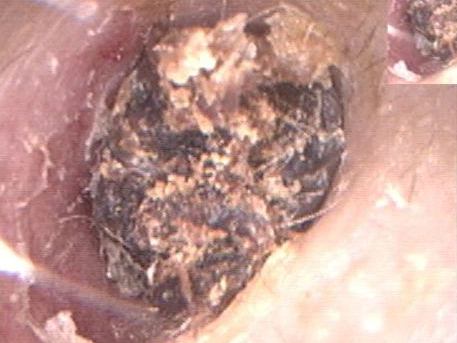

最后林大爷因为右耳剧痛、耳道流血才不得不去医院,医生确诊为耳道异物合并急性中耳乳突炎,还在他耳朵里取出了70多条蛆虫!

▲图源:福建医科大学附属第一医院